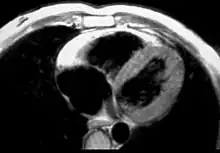

MRI

Fatty infiltration of the RV free wall can be visible on cardiac MRI. Fat has increased intensity in T1-weighted images. However, it may be difficult to differentiate intramyocardial fat and the epicardial fat that is commonly seen adjacent to the normal heart. Also, the sub-tricuspid region may be difficult to distinguish from the atrioventricular sulcus, which is rich in fat.

Cardiac MRI can visualize the extreme thinning and akinesis of the RV free wall. However, the normal RV free wall may be about 3 mm thick, making the test less sensitive.